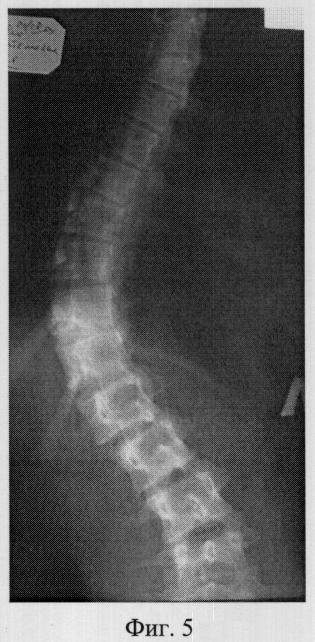

Фиг.5 – рентгенограмма в прямой проекции сколиотически измененного позвоночника больной M. до операции (грудная локализация);

В СарНИИТО ей была выполнена рентгенография в стандартных проекциях: фасная (фиг.5) и боковая (фиг.6) рентгенограммы.

По фасной рентгенограмме определены показатели позвоночника:

– угол сколиотической деформации по Кобб: стоя – 63°, лежа – 48°;

– индекс стабильности по Казьмину – 0.87;

– определена протяженность дуги в 12 позвонков (от Th5 до L4),

– определена вершина деформации – Th11.

По рентгенограммам проведена оценка зрелости позвоночника: тест Риссера составил R-4, кольцевые апофизы тел позвонков не определяются на фоне тел по всей дуге искривления, что свидетельствует о завершенности роста больной.

В связи с протяженностью сколиотической дуги в 12 позвонков, локализацией центральной дуги в грудопоясничных отделах, завершенности роста больной сделан вывод о возможности проведения дорсальной коррекции сколиотической деформации и фиксации позвоночника из заднего доступа с созданием заднего спондилордеза.

Определили патологическую ротацию позвонков сколиотической дуги. Показатель патологической ротации на вершине деформации Th11 не превысил 43°, поэтому установка транспедикуллярных винтов не оправдана.

Заключение: необходимо проведение оперативной дорсальной коррекции и фиксации позвоночника двустержневой полисегментарной типа CDI «Horizon» фирмы «Medronic» с использованием дополнительных субламинарных проволочных петель